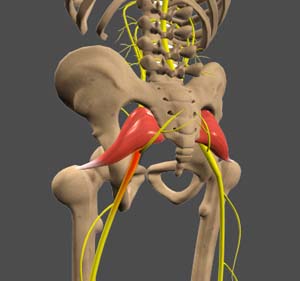

What is the Sciatic Nerve?

The sciatic nerve is found in the lower back and runs down the leg. There is one on the right and one on the left. It is rare the sciatic nerve itself is irritated, but more commonly, it is nerves that make up the sciatic nerve that is compressed. Typically, the nerves at L4, L5, and/or S1 are affected.